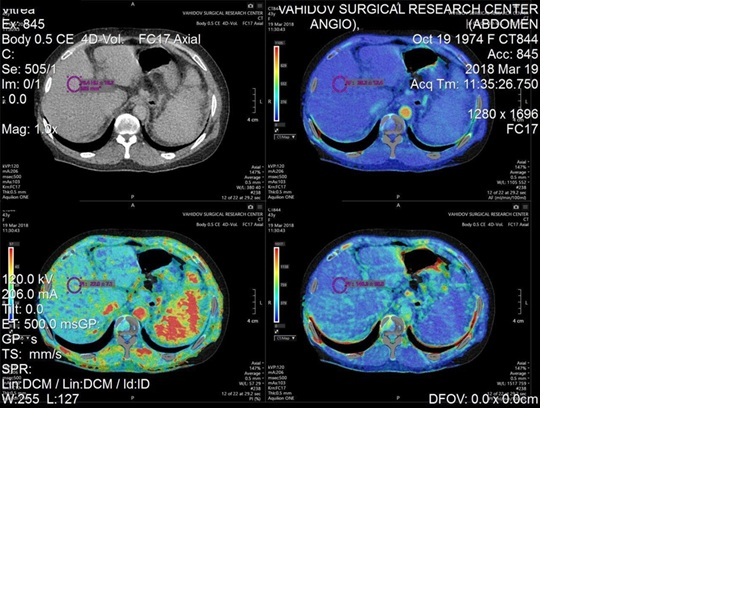

As demonstrated in Figures 5 and 6, the sample indicators of liver perfusion are shown in both health and LC states. It is also important to note that MSCT examinations allow for the identification of the particular features of the portal system angioarchitecture. This is important in the planning of surgical options, including palliative surgeries such as portosystemic shunting or disconnecting interventions, as well as definitive treatment, i.e. liver transplantation. The visualisation of vasculature facilitates the identification of distinctive features in the architecture of the portal and arterial systems.